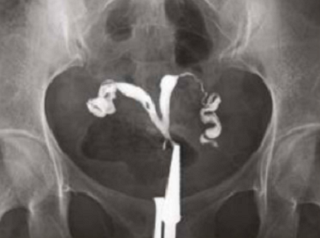

What does HSG assess?

Shape of the uterus

Normal shape

Unicornuate uterus

Complete septate uterus

Patency of fallopian tubes

Open tube

Closed tube

Uterine cavity

Clear/Normal

Submucosal fibroid

Adhesions/Synechiae